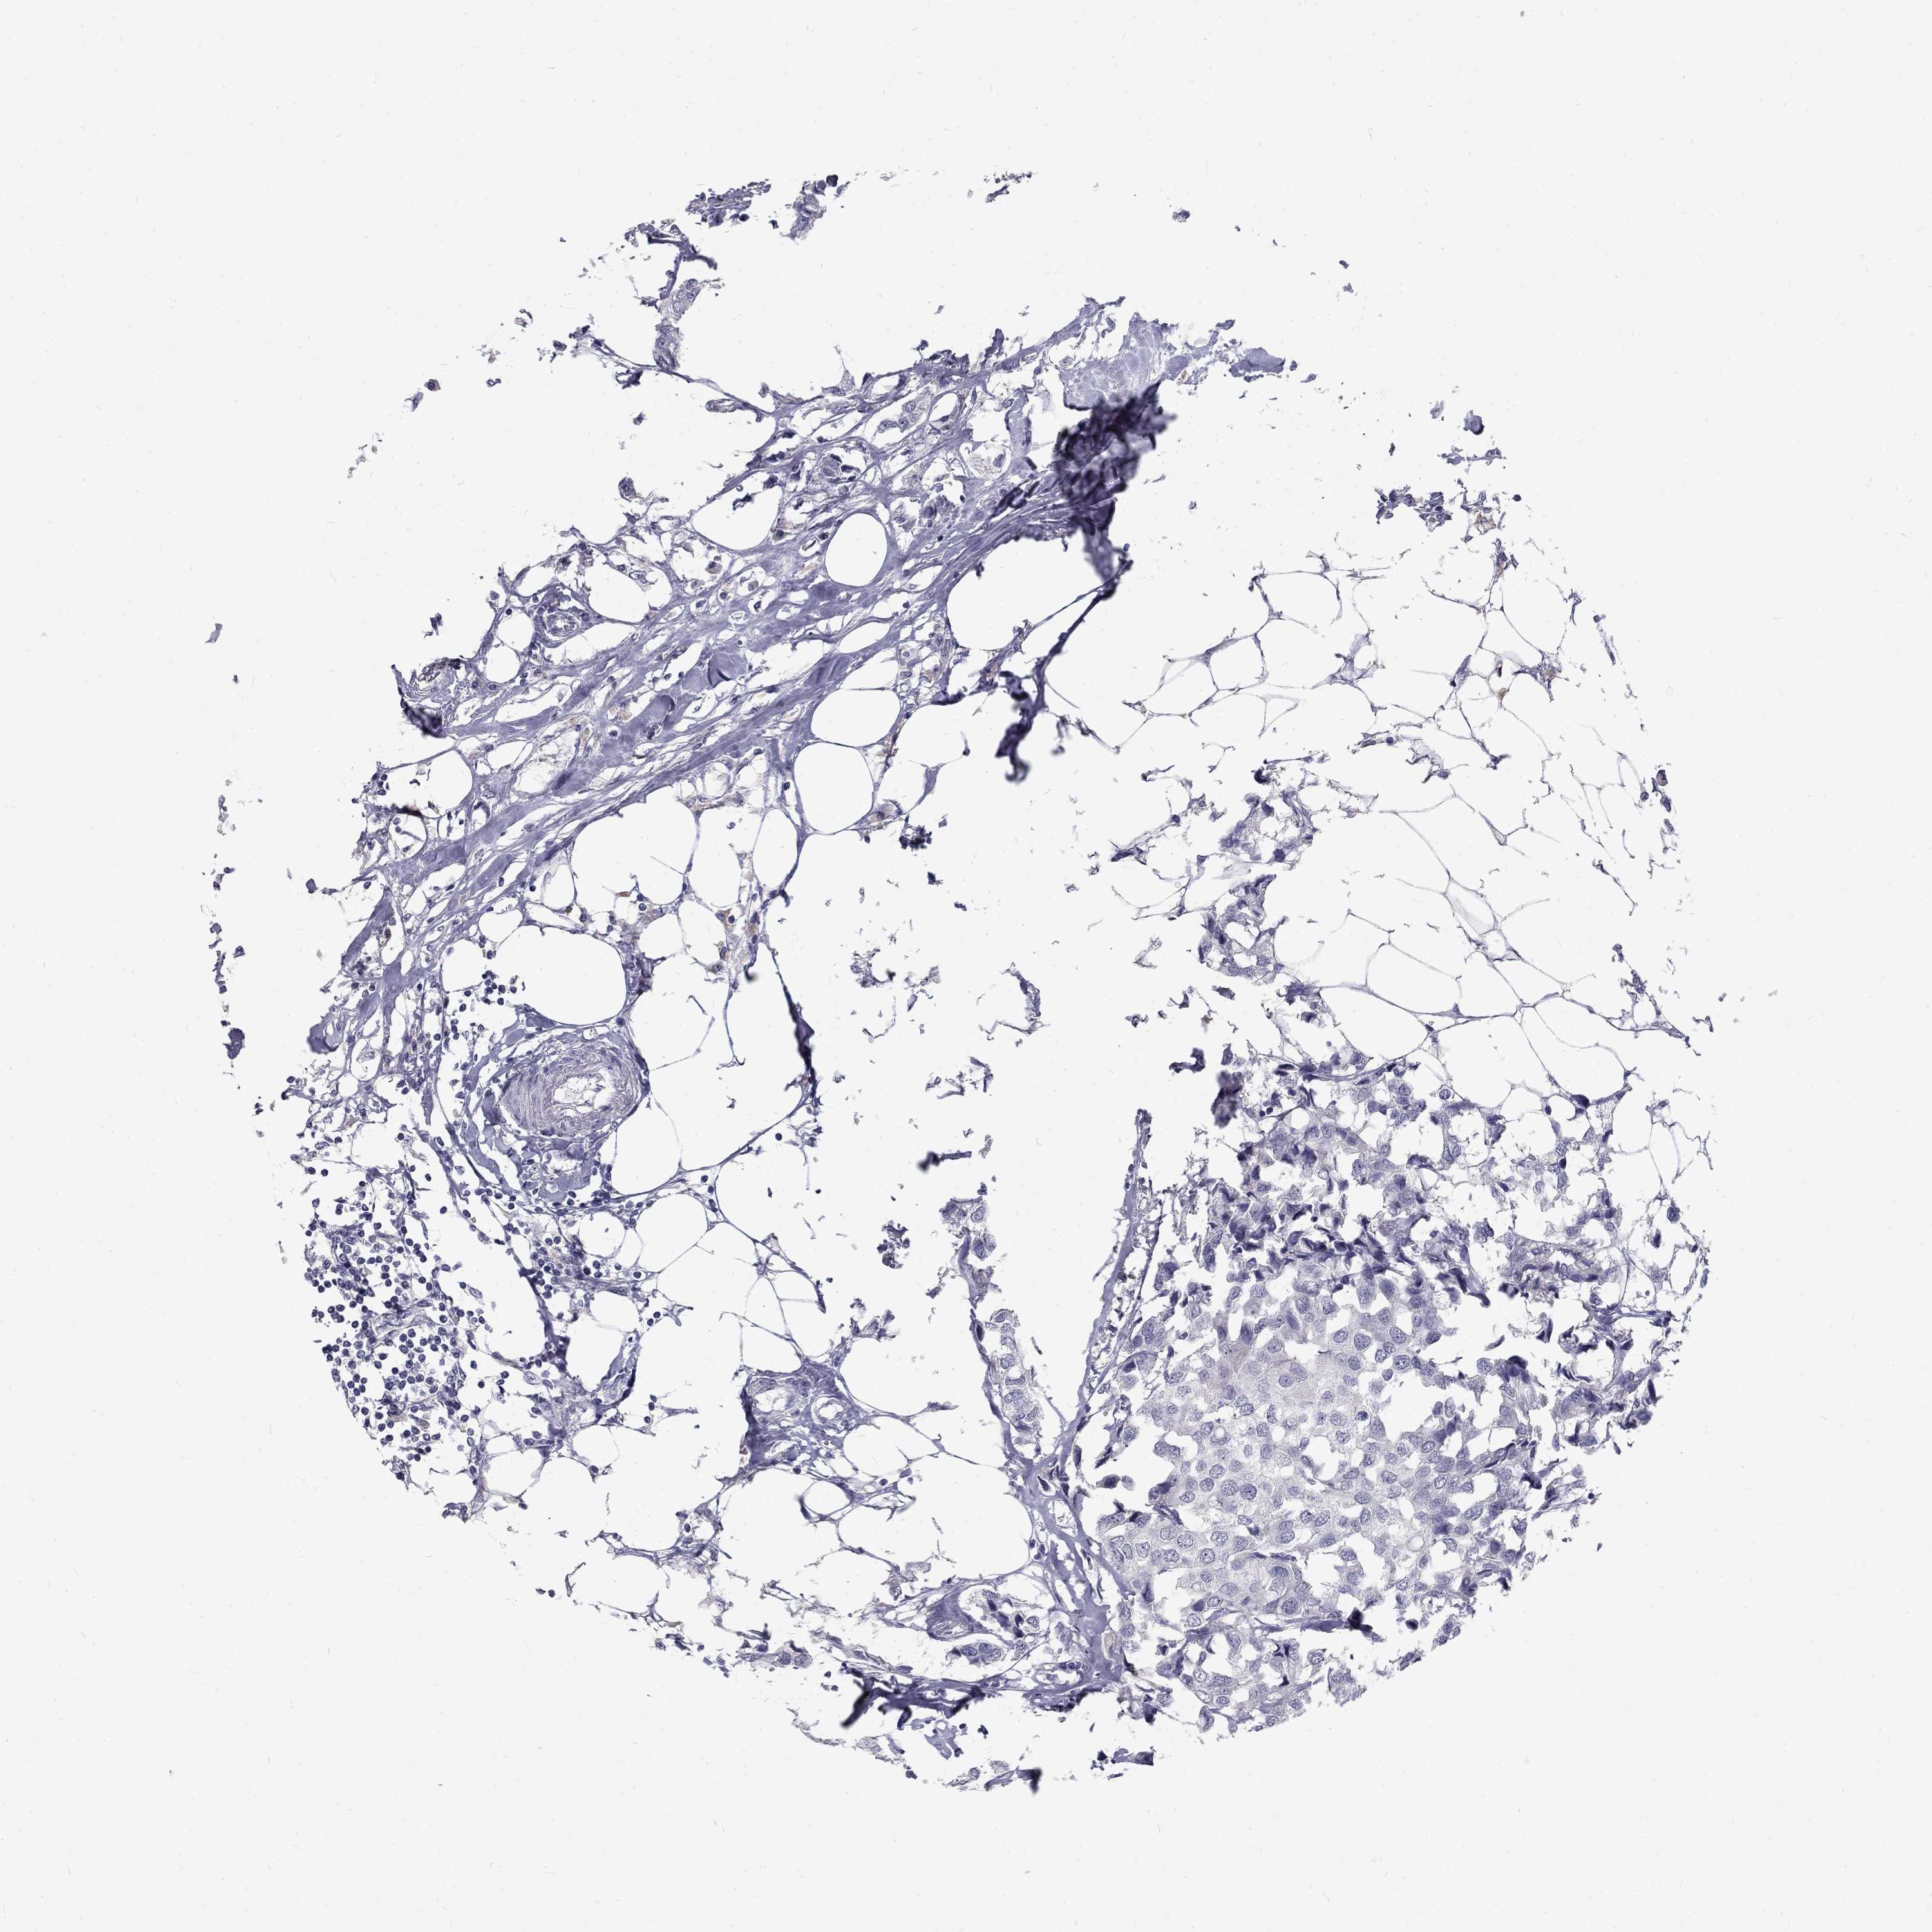

Breast cancer

Human cancer

Breast invasive carcinoma